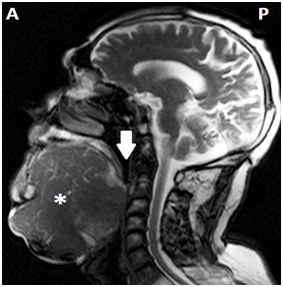

Sixty eight years old male patient was admitted to our clinic with the complaints of progressive swelling on neck which causes speech difficulty. He couldn’t close his mouth properly (Figures 1&2). It was learnt that he was only drinking fluids but could not eat solid meals for long years. In his physical examination, a mass lesion fulfilling mouth base and all oral cavity pushing the tongue to the posterior was observed. This mass was filling all submental and submandibular regions bilaterally on neck and it were running over the secondary regions. The mass was soft in palpation and was approximately 20x10cm in dimensions. The patient’s tongue movements could not be detected due to size of the mass but his flexible endoscopic examination and other ear- nose- throat examinations were normal. In magnetic resonance imaging (MRI), a conglomerated, highly contrast enhanced mass lesion with an approximately 20 cm diameter that was narrowing the upper airways, considerably widespread on submental region, at the 2nd region level on bilateral parotid and submandibular regions was detected (Figure 3).

Figure 3 Sagittal T1 scan MRI of the patient. A, Anterior; P, Posterior; *, Mass; White Arrow, Pharynx.